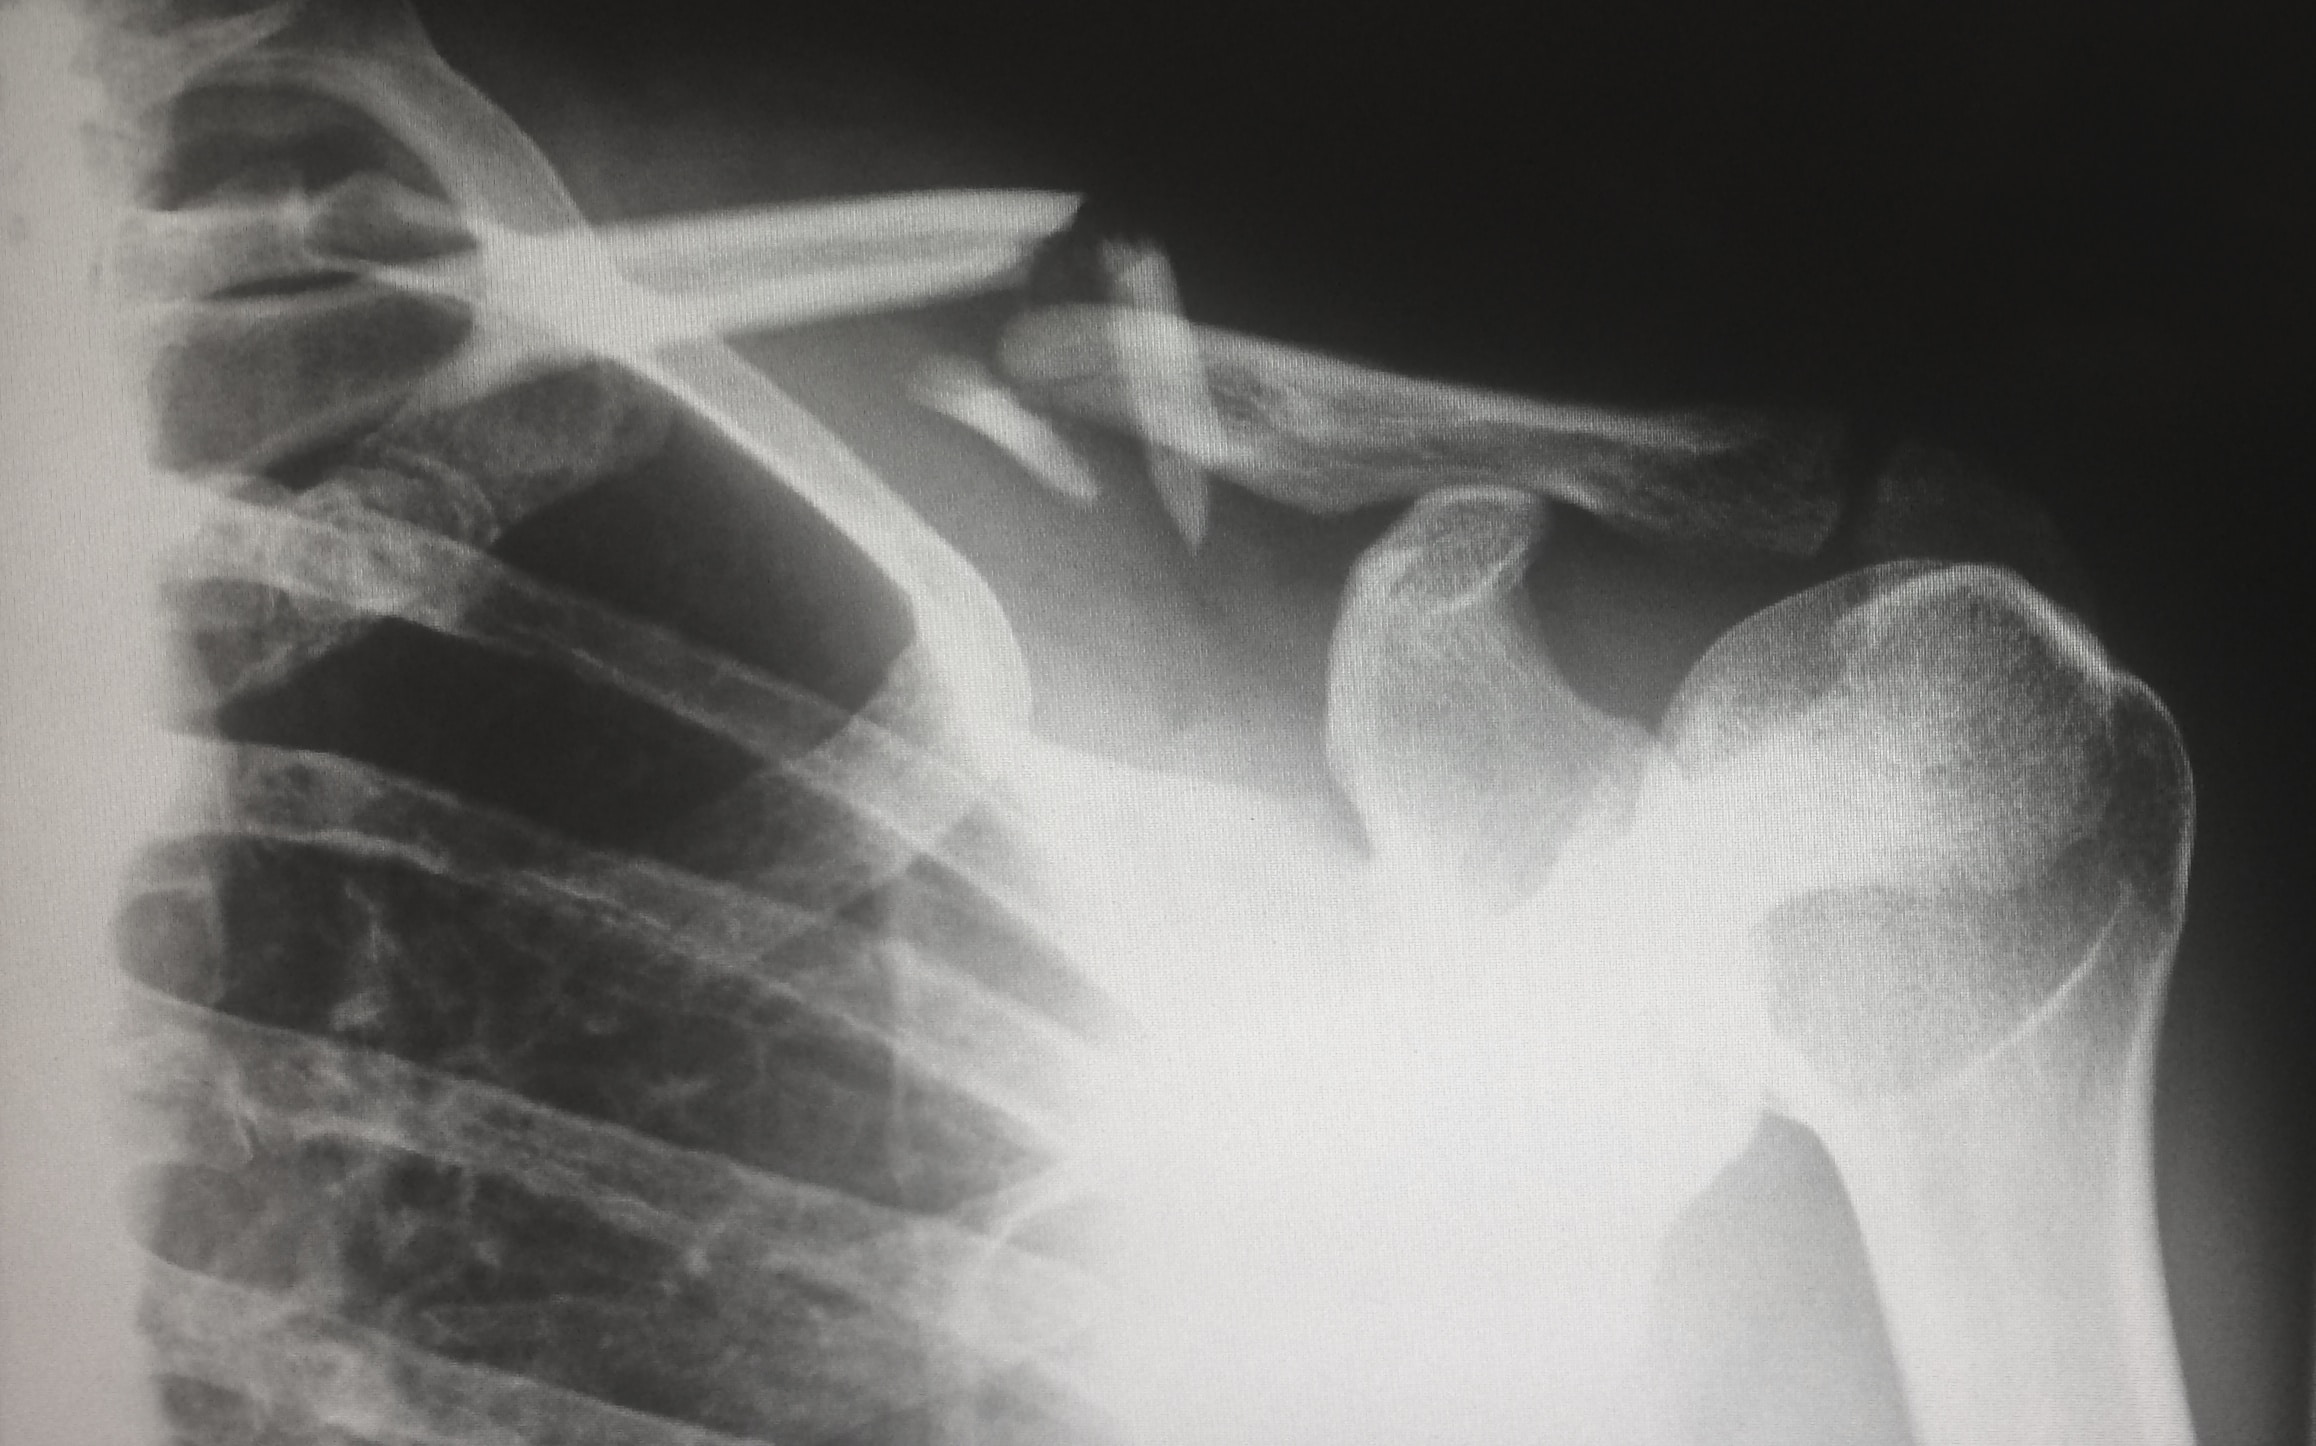

오십견, 더 널리 알려진 이름으로 견갑골 증후군 또는 견갑골 결림 증후군은 견갑골(어깨뼈) 주위의 힘줄(건)이 염증이나 손상을 입어 발생하는 상태로, 주로 견갑골 부위에서 흔히 발생합니다. 오십견의 증상은 다음과 같을 수 있습니다.

1. 힘줄(건)의 염증 또는 손상: 어깨 부위의 힘줄이 염증이나 손상을 입으면 통증이 발생할 수 있습니다. 특히, 견갑골 주위의 힘줄이나 회전근개 부분에서 문제가 발생할 경우 오십견이 발생할 수 있습니다.